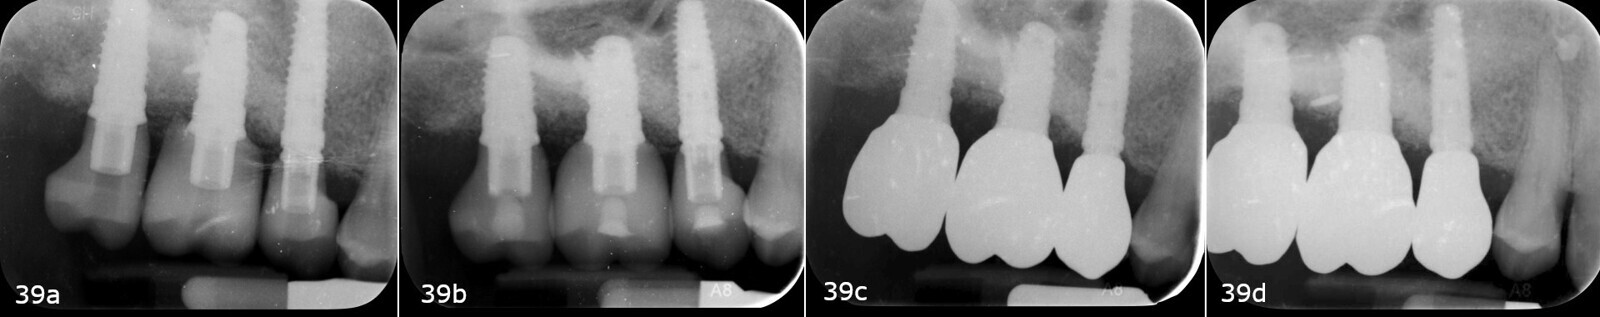

After three months, the implants were exposed through an apically positioned flap to increase the amount of keratinised tissue on the vestibular side of the implants and to realign the mucogingival junction, previously shifted towards the palate. Flared healing screws were placed to promote proper transmucosal healing. After one month, single ceramic crowns were placed for the first functional loading and temporary restoration while waiting for complete bone maturation (Fig. 34). After six months, the crowns were replaced with zirconia crowns for the final functional loading and the definitive restoration (Figs. 35–38). Clinical and radiographic follow-ups at the first functional loading, at six months, 12 months and 24 months showed the health of the peri-implant tissue and the maintenance of peri-implant bone levels (Figs. 39a-d).